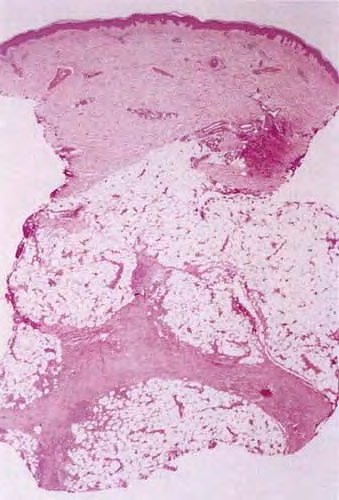

Histopathology. The histologic changes are present mainly in and near the septa of the subcutaneous tissue .

. The overlying dermis often has only a minimal to moderate, superficial and deep perivascular lymphocytic infiltrate.

Later lesions of acute erythema nodosum show widening of the septa, often with fibrosis and with inflammation at the edges of the septa and involving the periphery of the fat lobules . Neutrophils usually are absent, and the vascular changes are less prominent than in early lesions. There are more macrophages in the infiltrate. Macrophages at the edges of the fat lobules show phagocytosis of lipid from damaged adipocytes, and the small droplets of lipid in their cytoplasm give them a "foam cell" appearance. Granulomas formed by macrophages, without lipid deposition, are more frequent

when late lesions are compared with early ones . The granulomas often are loosely formed with macrophages predominating in a focus with multinucleated giant cells. Occasionally, well-formed, discrete sarcoidal granulomas occur in small numbers in the septa. The multinucleated cells usually have an irregular distribution of the nuclei in the cytoplasm. The oldest lesions have septal widening and fibrosis with a decrease in all of the inflammatory cells.

In chronic erythema nodosum, the histologic findings are generally similar to those of the late stages of acute erythema nodosum. However, granulomas and lipogranulomas often are more pronounced in chronic erythema nodosum. There is vascular proliferation and thickening of the endothelium with extravasation of erythrocytes . In some instances, numerous well-formed granulomas can be found and consist of epithelioid macrophages and giant cells without caseous necrosis . Although significant degrees of vasculitis have been observed by some authors , others have found vascular changes to be slight or absent . The presence of thickened fibrotic septa with marked capillary proliferation and massive granulomatous reaction have led several authors to consider erythema nodosum migrans as an entity separate from the late lesions of acute erythema nodosum . Other authors consider all of these histologic patterns to be included within the spectrum of chronic erythema nodosum .